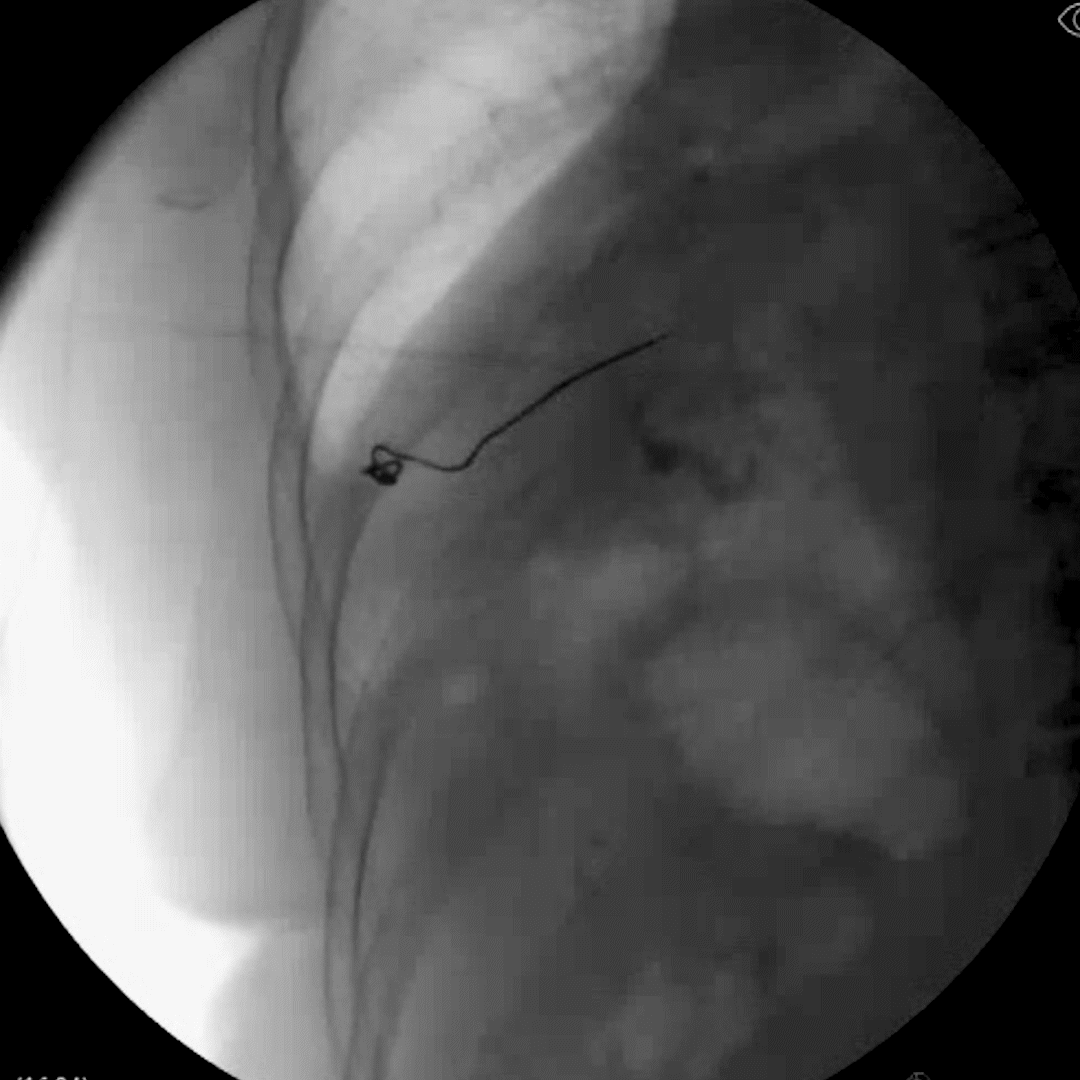

An Injectrode placement procedure for the SPG was devised to maximize patient comfort for transcutaneous stimulations.

We developed a procedure in which the delivery needle was inserted inferior to the zygomatic arch and anterior to the mandible. Then, the needle was advanced toward the pterygopalatine fossa until contact was made with the lateral pterygoid plate. The point of entry under the earlobe allows patients to apply stimulation readily through a surface patch.

Movement of the head in flexion and extension, lateral rotation, and opening and closing of the mouth for repeated cycles led to negligible movement of the stimulator and collector ends.

This approach is a promising first step in demonstrating how the Injectrode can be used to treat craniofacial pain.